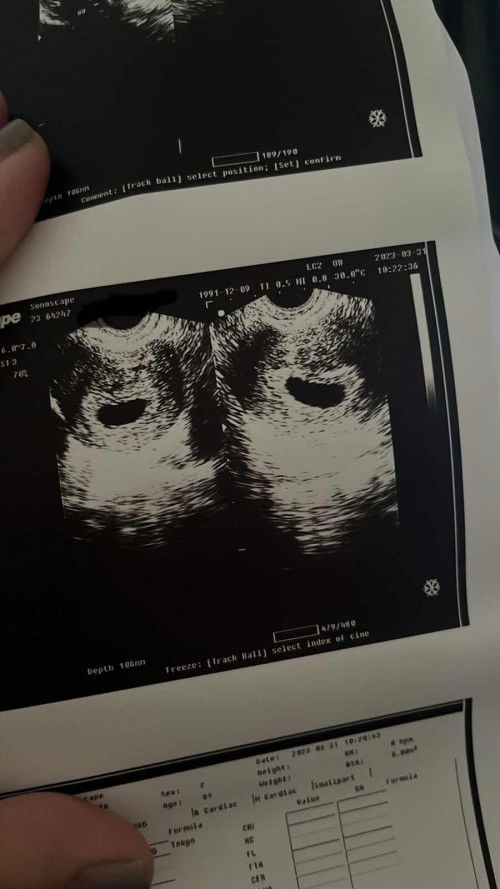

Blighted Ovum

We’re so devastated right now, 2 consecutive unsuccessful pregnancy ko na. Huhu meron po bang nagka anak pa after 2 mc? Apas positive po ba kayo? Need ko daw po magpa apas panel to check bakit nangyayari ito :( ano po ginawa para malabas nyo ung dapat ilabas? 7th week ko po sana pero wala pong nakitang kahit ano kundi sac lang :(